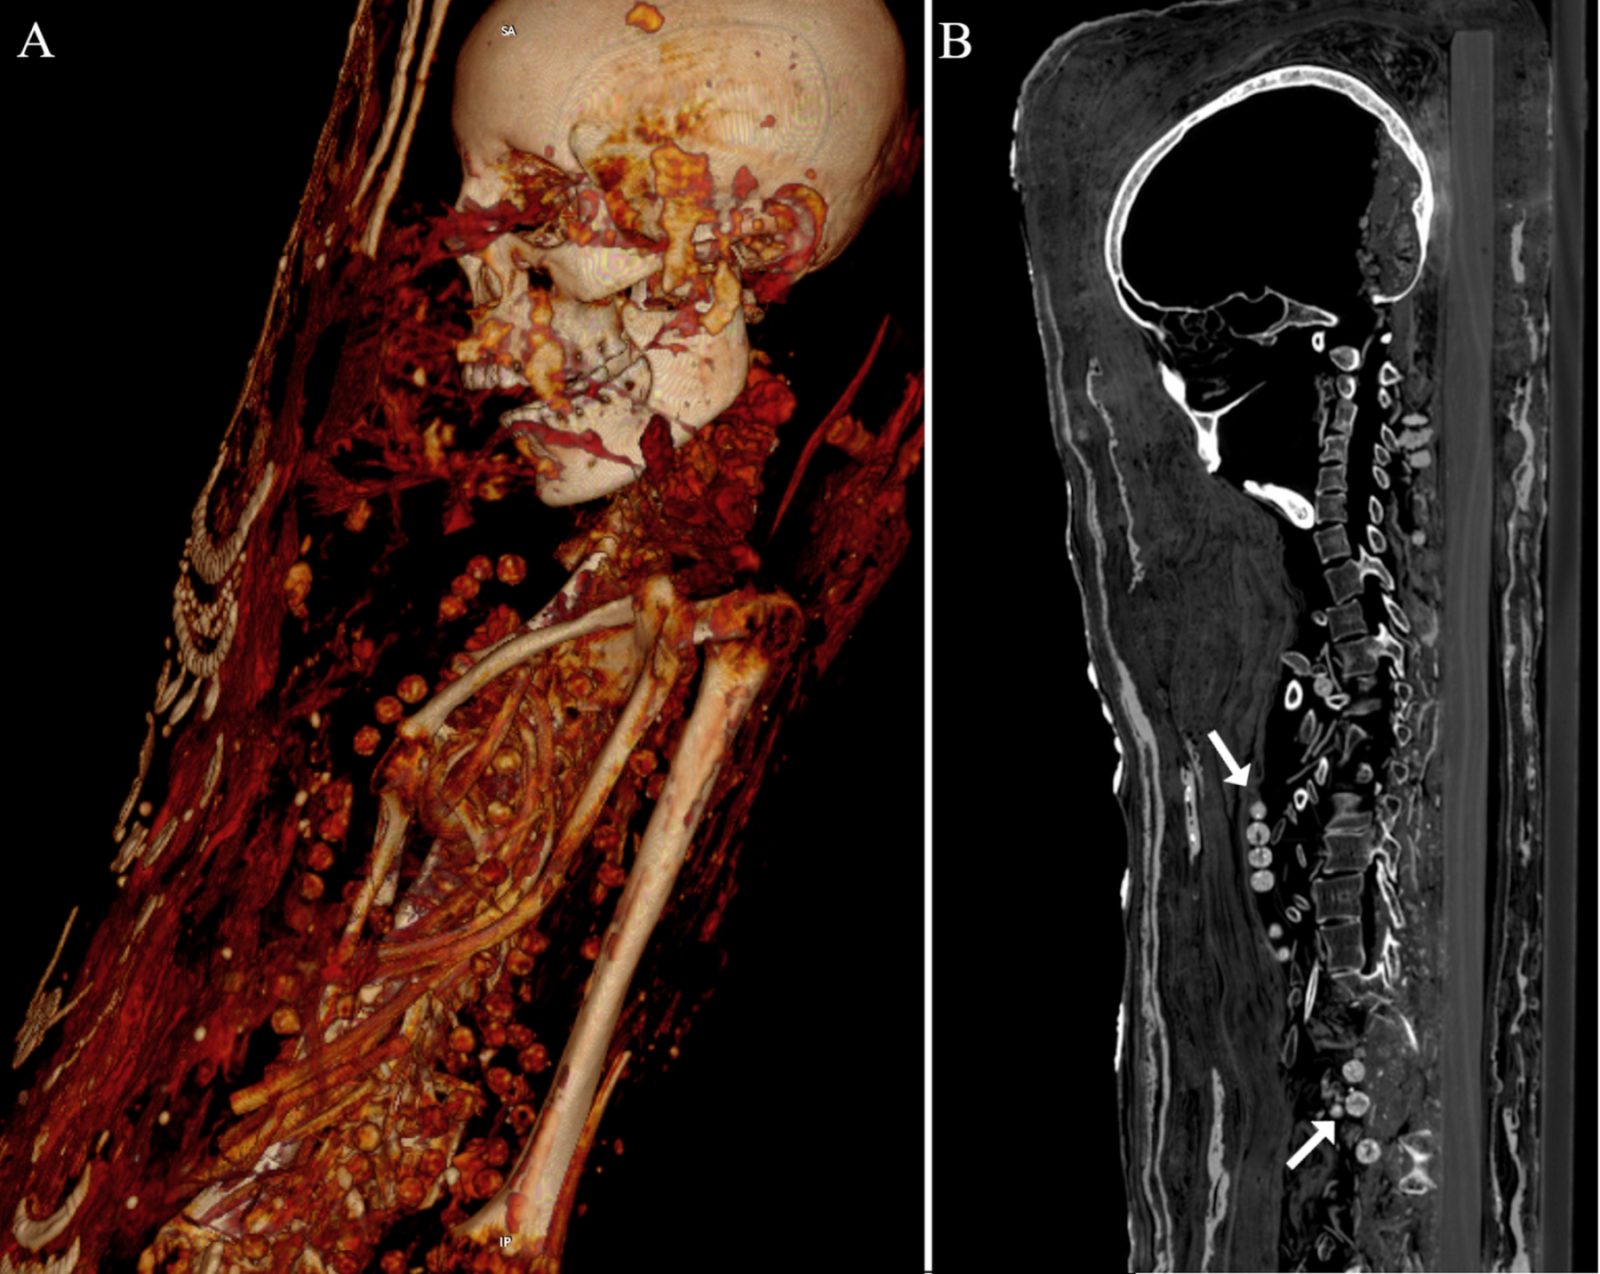

(A) sagittal multi-planar reconstruction; (B) coronal multi-planar reconstruction.. Zesch S, et al. PLOS One / CC BY 4.0

As reported last month, they are a man, woman and teenage girl, each with an interesting story to tell. A team, including Egyptologist Dr Stephanie Zesch, gave the bodies a CT (Computed Tomography) Scan, publishing the findings on the PLOS One open access science journal.

Writing in PLOS One, the team comment: “Due to the rather poorly preserved bodies of the male and middle-aged female, a specific technique of artificial mummification could not be ascertained.”

Thankfully, enough could be seen via the CT scan to draw some conclusions. The man is approx 30 years of age, with a height of 5 ft 4 ins.

He’d also been roughed up, though not by his Egyptian contemporaries. Some bones are in disarray, with breakages. This suggests a person, probably from the 17th century, handled him badly.

As for the woman, she appears to be in middle age. Standing at 4 ft 11 ins, she had arthritis in her left knee. Both were mummified with their organs, as was the approach back then. Death was no barrier to Ancient Egyptian life. Details such as coins to pay Charon, ferryman to the afterlife, are in evidence.

The brains of the couple have perished. Yet the teenager’s grey matter is preserved reasonably well, except for shrinkage. 5 ft 1 ins tall, she wore a hairpin.

She wound up in Cairo, at the Museum of Egyptian Antiquities. On a morbid note, she was afflicted with a tumor in her spine.